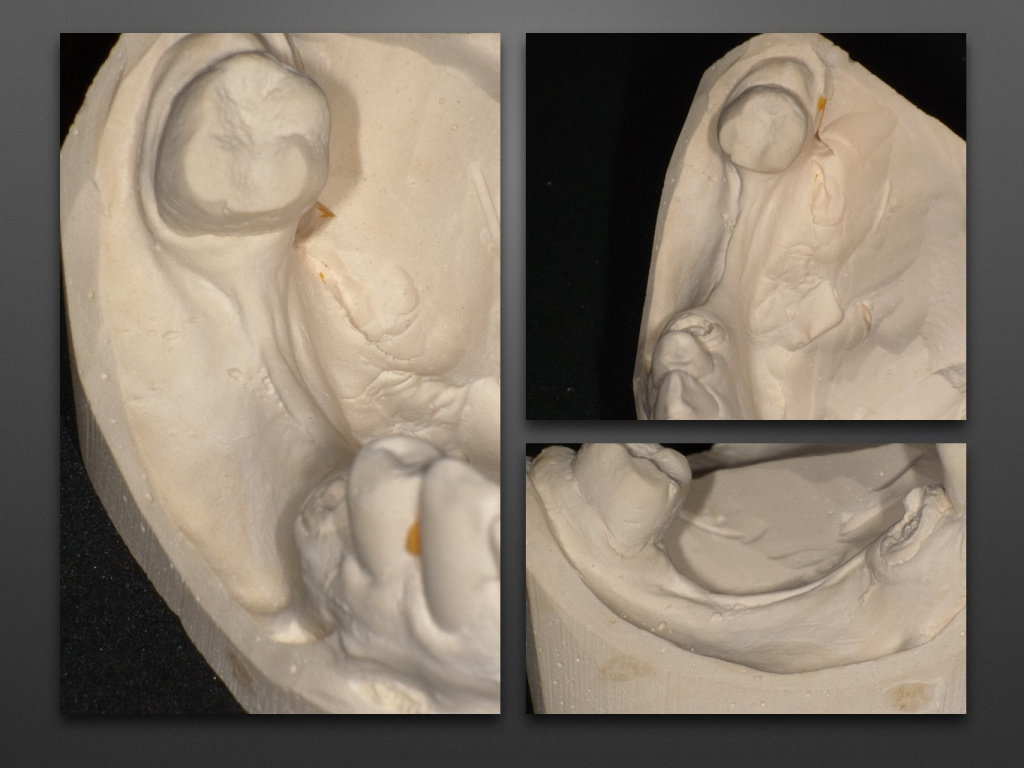

Горизонтальное увеличение альвеолярного отростка (остеоматрикс, биоимплант ГАП + пластина)